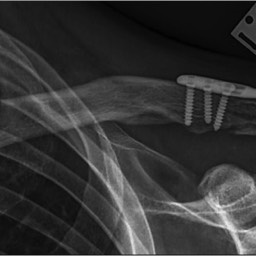

Generally all displaced fractures of the distal clavicle require surgery to increase the incidence of union. In my practice, the operation is performed by realigning the bones back to their original position using a plate and screws on top of the bone. The advantage of fixing them with a plate and screws generally means that you can start to move the arm a lot quicker and to also decrease the incidence of non-union.

How is the Operation Done?

The operation is performed with the patient under a general anaesthetic, in other words, completely asleep, and a small 3-4 cm incision is made under the collarbone, at the end of the shoulder. The fractured bone ends are exposed and put back into position using a plate and screws as shown below.

Click an image to enlarge